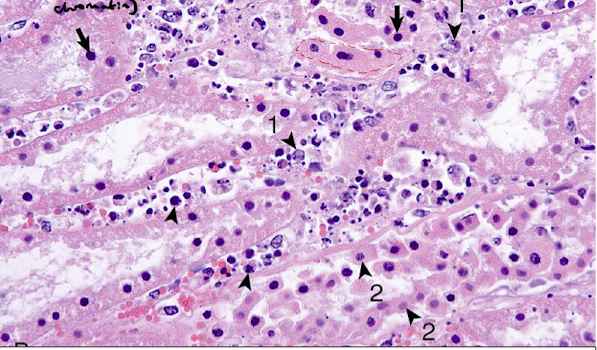

Name and describe the processes that are occuring below:

Arrows:

Arrowhead:

Arrowhead 1:

Arrohead 2:

Arrows: nuclear pyknosis- irreversible condensation of the chromatin

Arrowhead: karyorrhexis - fragmentation of the nucleus

Arrowhead 1: karyolysis - dissolution of the cells nucleus

Arrohead 2: cells eosinophilic, shrunken, lose adherance to the BM